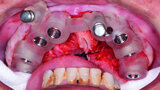

Fig. 7: Surgical guide for maxillary implants.

Fig. 8: Surgical guide for mandibular implants.

Fig. 9: Placement of maxillary surgical guide.

Fig. 10: Paralleling pins placed.